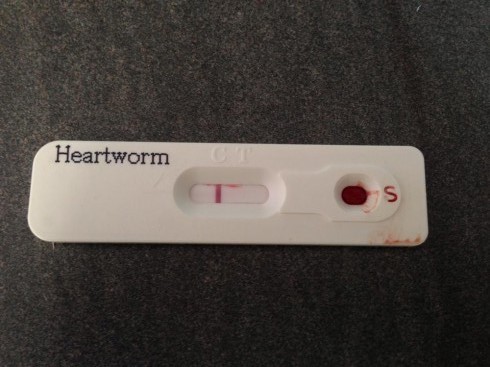

A kutyák fertőzöttségének megállapítására rutinszerűen két módszert alkalmaznak. Egyrészt a kifejlett, megtermékenyített nőstény által a véráramba bocsátott első stádiumú lárvákat, úgynevezett mikrofiláriákat keresnek a vérkenetben mikroszkópos vizsgálattal. Azokban a napszakokban, amikor várhatóan nagyobb a szúnyogcsípés valószínűsége, ezek a lárvák kivándorolnak a hajszálerekbe, hogy minél több esélyük legyen szúnyoggal találkozni, és annak a testében tovább fejlődni. Ezek a legnagyobb eséllyel az esti órákban vett, hajszálerekből származó vérmintában lelhetőek fel. Pozitív vizsgálati eredmény még nem feltétlenül jelenti azt, hogy az állat szívféreggel fertőzött. Egy rokon faj, a bőrférgességet okozó Dirofilaria immitis is hasonló módon fejlődik, és a megtévesztésig hasonló küllemű mikrofiláriákat bocsát a véráramba. A szívférgesség kimutatására rutinszerűen alkalmazott másik módszer egy, a kifejlett nőstény szívféregben megtalálható anyag gyorsteszttel történő kimutatása a vérből. Ez a vizsgálat az állatorvosi laboratóriumok mellett már a legtöbb rendelőben is elérhető. A gyorstesztekhez mindössze 1-2 csepp vérre van szükség a kutyától, az eredmény 10 perc alatt megvan. Kétes esetben érdemes lehet más gyártó gyorstesztjét is igénybe venni, illetve a szívféreg DNS-ét kimutató laboratóriumi PCR vizsgálatot végeztetni. Ez utóbbi az elérhető legpontosabb, egyben sajnos a legköltségesebb vizsgálati eljárás.

Kép:dogomentes.hu